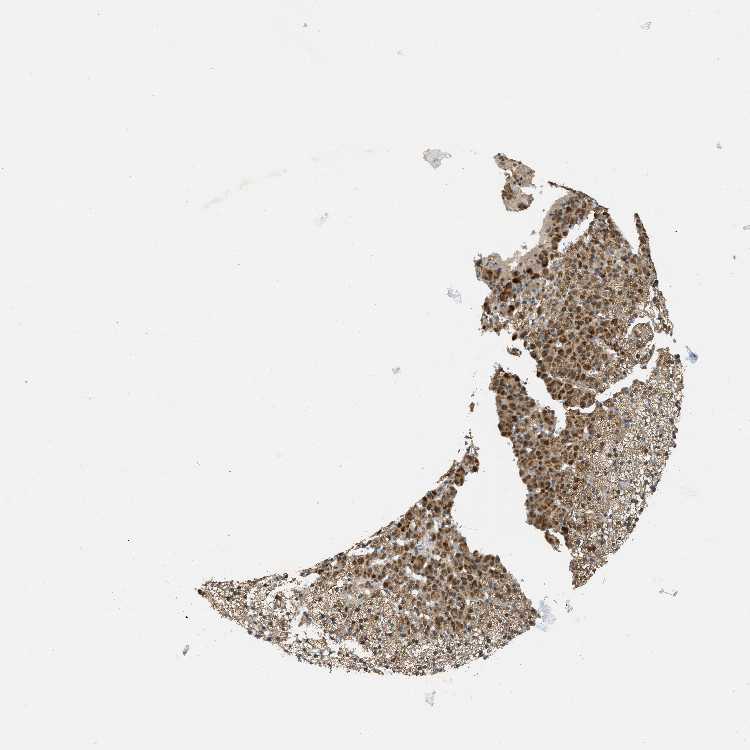

ADRENAL GLAND - Antibody stainingi

Antibody staining in the annotated cell types in the current human tissue is reported as not detected, low, medium, or high, based on conventional immunohistochemistry profiling in selected tissues. This score is based on the combination of the staining intensity and fraction of stained cells.

Each image is clickable and will lead to virtual microscopy that enables deeper exploration of all samples and also displays staining intensity scores, fraction scores and subcellular localization as well as patient and tissue information for each sample.

Antibody HPA036786Antibody CAB017849

Glandular cells MediumMedium